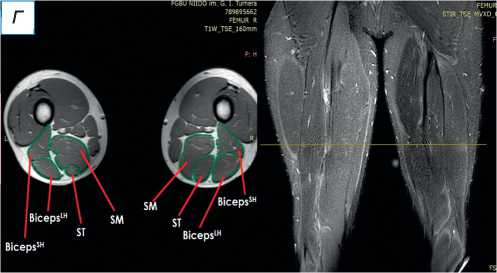

При поступлении в центр пациенту выполнены лучевые методы исследования нижних конечностей, в частности панорамная рентгенография и компьютерная томография (КТ) нижних конечностей; сравнительная МРТ мягких тканей правого и левого бедра (рис. 2). По данным рентгенографии и КТ-исследования, костно-суставной патологии не обнаружено. По результатам МРТ определены повреждения всех трёх мышц различной степени тяжести — SM, ST, BicepsLH (расположены в порядке убывания; см. рис. 2, а ). Длинная головка двуглавой и полусухожильная мышцы, вероятно, были оторваны у места крепления и не подверглись значительной ретракции; начало брюшка полуперепон-чатой мышцы визуализировано на границе верхней и средней трети бедра (ретракция 9 см).

Рис. 2. Сравнительная магнитно-резонансная томография мягких тканей правого и левого бедра (аксиальные и фронтальные срезы): а — изменение нормальной архитектоники полусухожильной, полуперепончатой и длинной головки двуглавой мышцы на уровне верхней трети правого бедра; б — на данном уровне не прослеживается мышечное брюшко полуперепончатой мышцы; в — на границе верхней и средней трети прослеживается мышечное брюшко полуперепончатой мышцы, спаянное с большой приводящей; определяется разница по форме и диаметру поперечника полусухожильной мышцы; г — на уровне средней трети отчётливо проявляются мышечное брюшко полусухожильной мышцы, несоответствие поперечного диаметра полуперепончатой и полусухожильной мышц с контралатеральной стороной, гипертрофия короткой и длинной головки бицепса; д — аналогичная картина и на границе средней и нижней трети. ST ( m. semitendinosus ) — полусухожильная мышца; SM ( m. semimembranosus ) — полуперепончатая мышца; BicepsLH ( m. biceps femoris ) — длинная головка двуглавой мышцы.